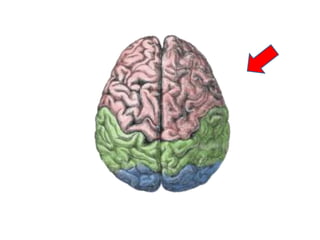

Ways of thinking about the brain

• Left to right

• Top to bottom

• Front to back